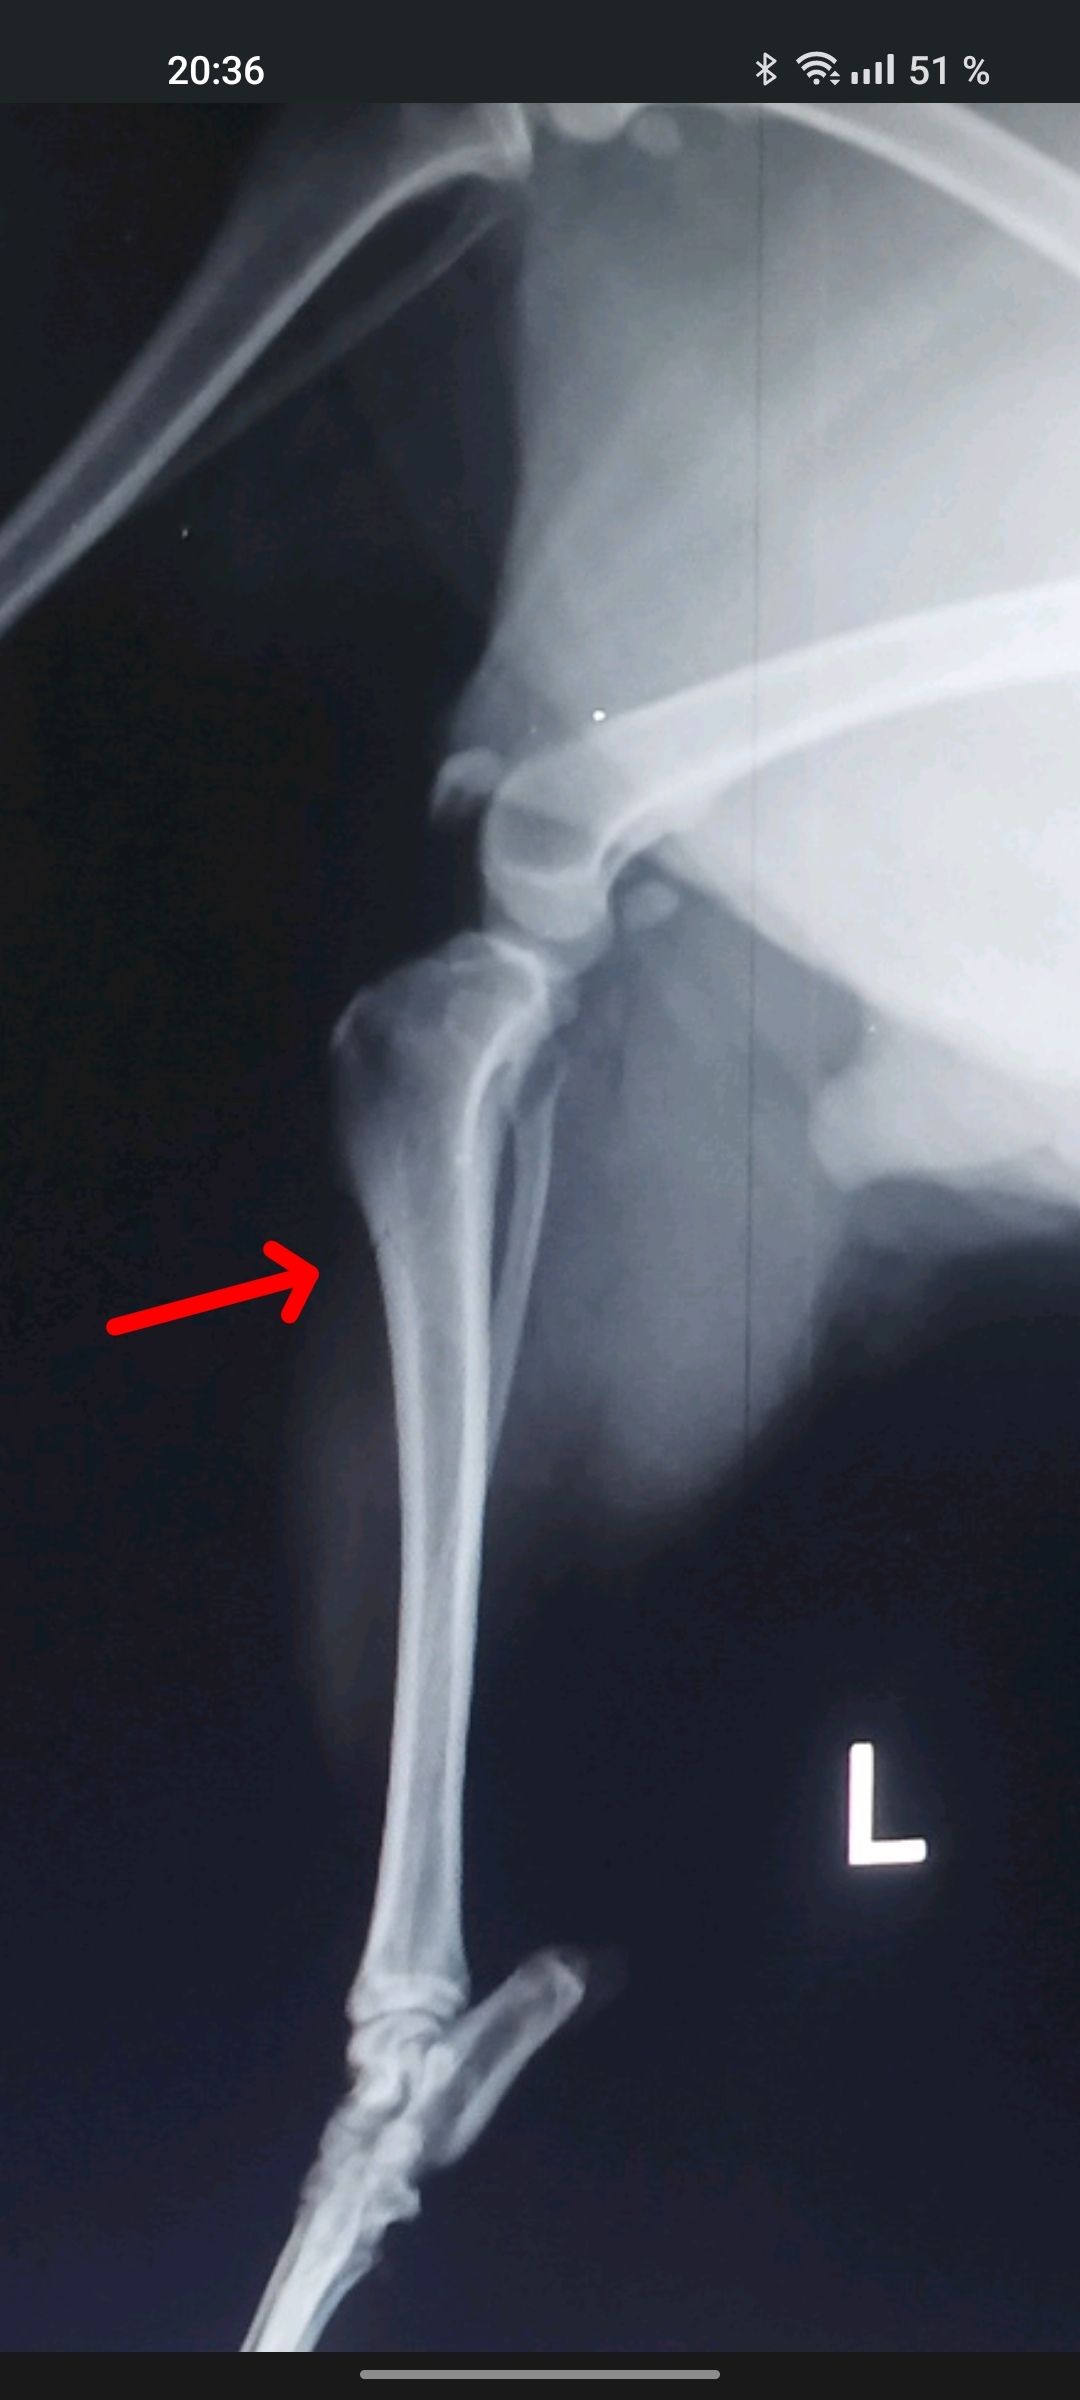

Вот же трещина есть, или это не страшно считается?

Иллюстрация к комментарию